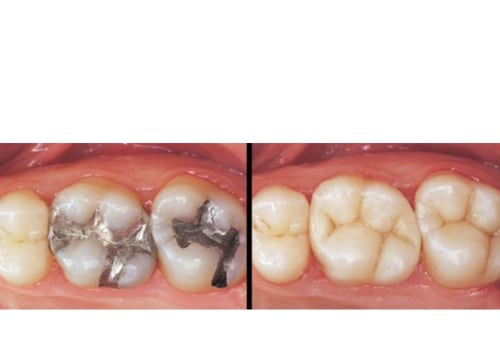

What is a filling on a tooth?

Tooth fillings are one of the most common procedures done by a Dentist near Johns Creek GA. They are used to treat...